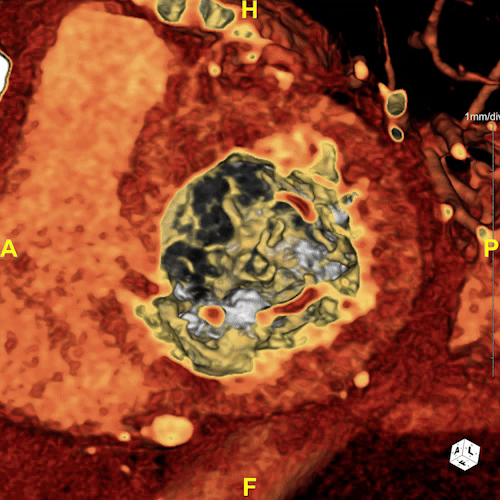

Figure A: 3D rendering of the patient’s heart. The blood–flow is shown in magenta and the mitral calcification in yellow.